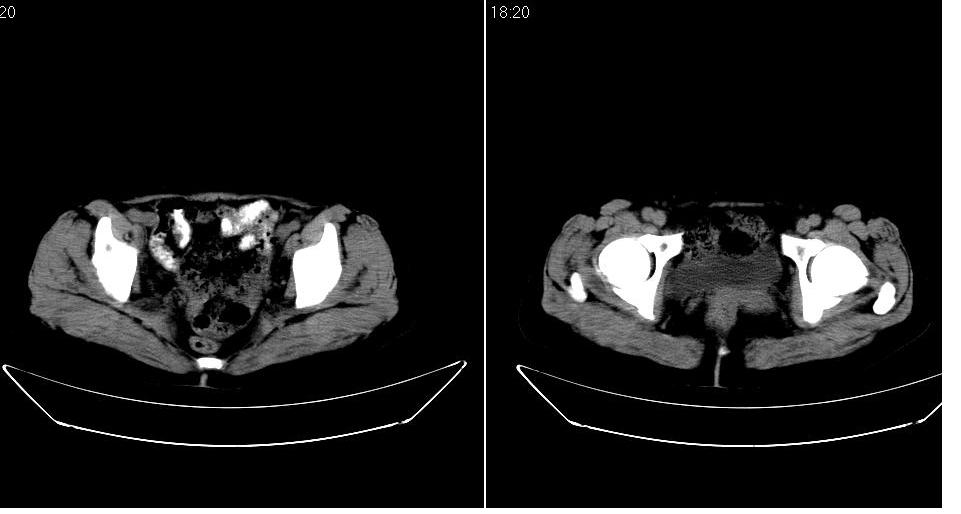

女 53岁,大便每天四到五次,变细,伴有粘液,病人家属说,去年五月在外院行子宫肌瘤术。

腹膜后多发肿大淋巴结肿大并融合改变;右侧回盲部可见团块样软组织影,不规则;

淋巴瘤?回盲部占位,,淋巴瘤肠道改变?建议进一步检查.

双侧盆腔均可见不规则形软组织肿块影,似为结节状影融合而成,但以右侧为甚,腹主动脉与下腔静脉周围亦可见多个肿大淋巴结.

结合临床手术史考虑:盆腔与腹膜后多发性淋巴结转移(原发灶可能是原来的\"子宫肌瘤\"恶变或并非\"子宫肌瘤\";回盲部肿瘤不排除)

支持。大便次数多可能系腹膜后肿大淋巴结累及肠腔所致。另外,可钡灌肠检查,进一步观察直肠及其他结肠有否异常。